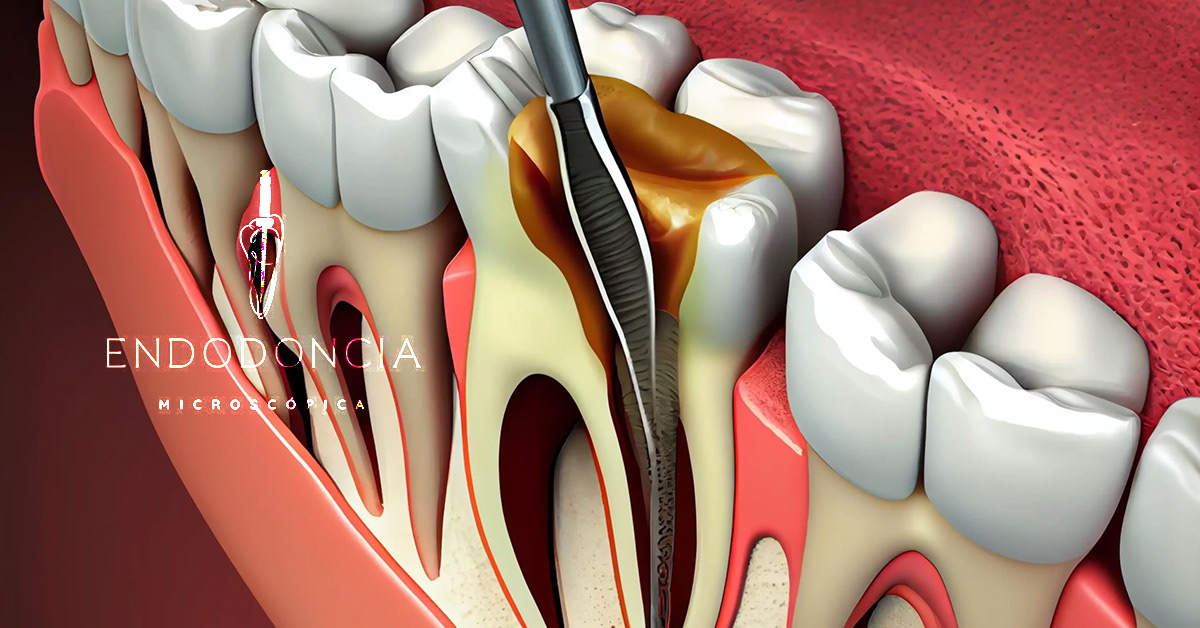

Tratamiento de conducto

Conservamos el diente natural extrayendo la pulpa afectada. Con anestesia local y aislamiento absoluto. Se sella tridimensionalmente el sistema de conductos con técnicas modernas de obturación para lograr un sellado hermético y duradero.